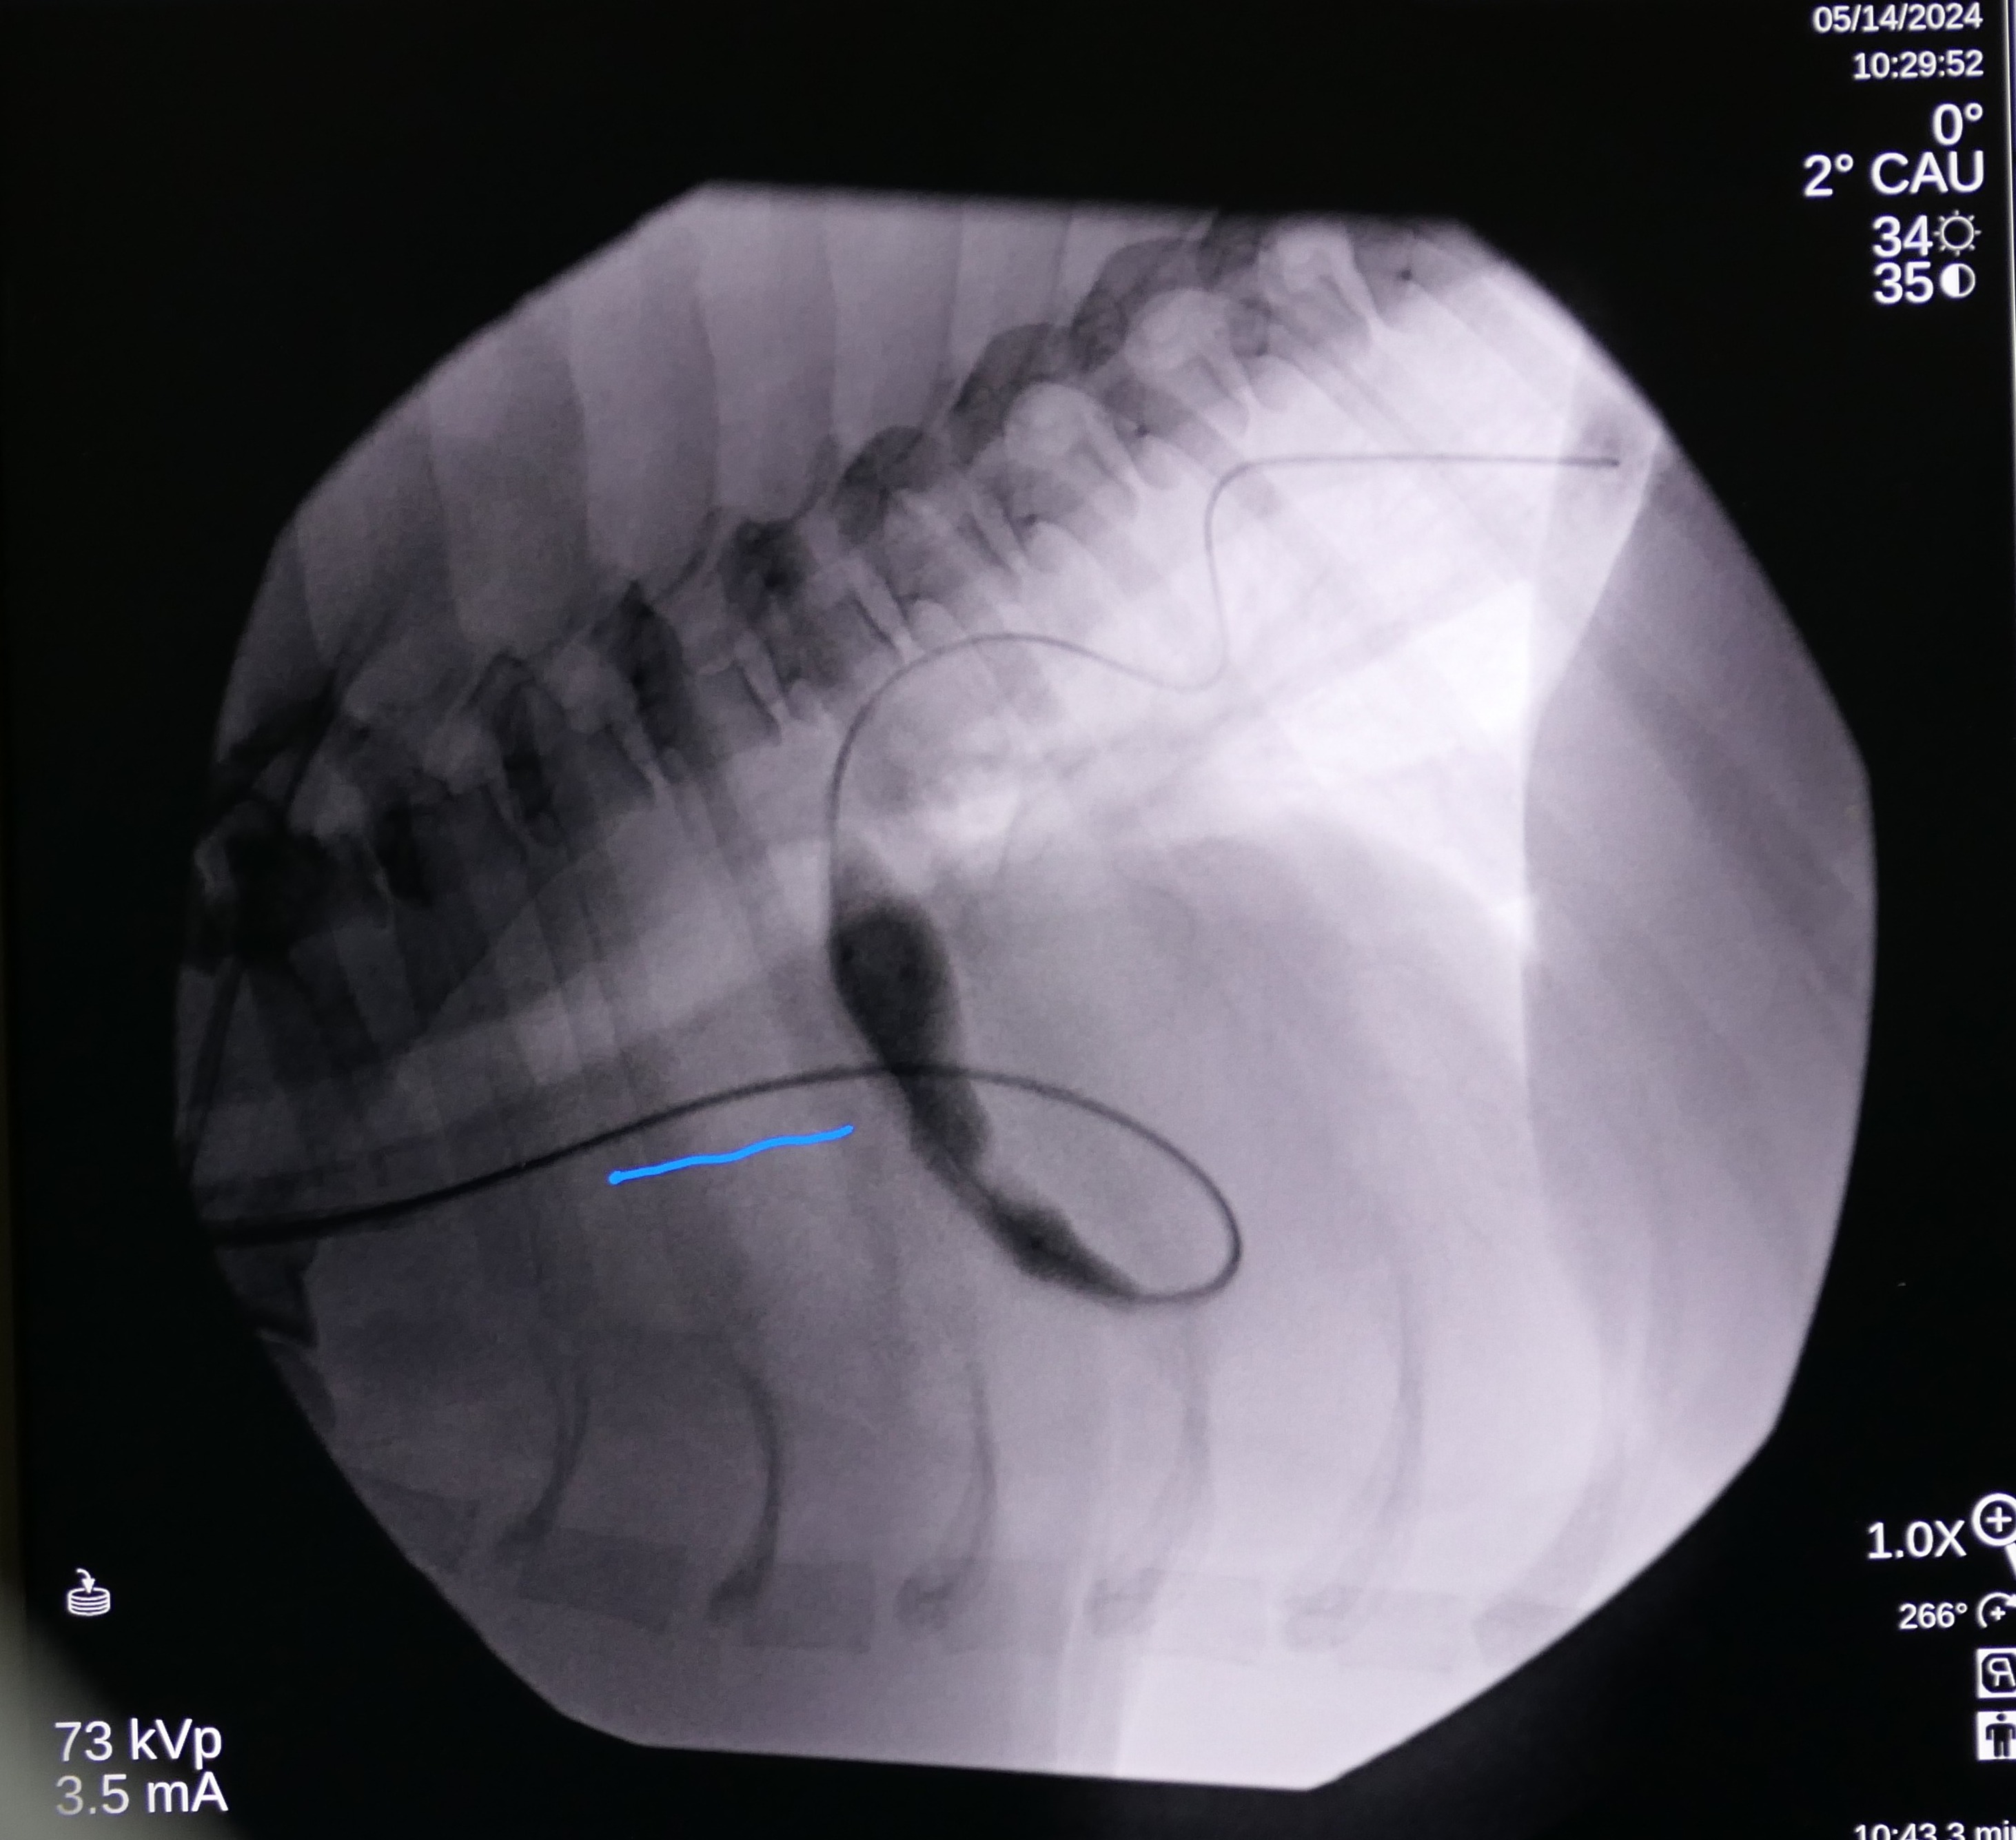

On May 7 2024, Snoop underwent a balloon valvuloplasty at MVRH. The procedure involved placing Snoop under general anesthesia and accessing the affected valve via the external right jugular vein. In order to gain access to the heart, a vascular introducer is first placed into the vein. This allows exchanging various wires and catheters without causing blood loss. Then, using fluoroscopy (Live X-rays) a catheter is advanced into the heart. This catheter has a small air balloon in its tip working as a “sail” and flowing downstream into the heart. Once the anatomy is assessed by using contrast, a Guire is placed to be used as a roadmap. Over this wire, a catheter with a large balloon in its tip is positioned across the fused valves. Once the balloon is inflated, the high pressures reached with this balloon separate the valve leaflets, decreasing the obstruction. This balloon reaches up to 18 atmospheres of pressure, and to put this in perspective, it is the equivalent of roughly stretching it with 260 pounds of force.